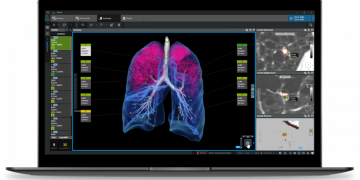

Read moreCoreline Smooth kündigt First China Partnership an Die südkoreanische medizinische KI -Firma Coreline Smooth hat seine erste Partnerschaft in China...